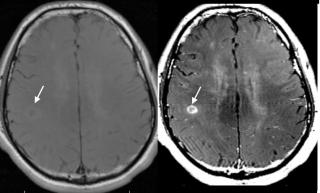

Ранняя диагностика БП затруднительна, благодаря сходству на ранних стадиях с эссенциальным тремором, мультисистемной атрофией и прогрессирующим надъядерным параличом. МРТ в диагностике паркинсонизма до недавнего времени рассматривалась в основном с точки зрения исключения или подтверждения заболеваний, вызывающих вторичный паркинсонизм - опухолей, субдуральных гематом, сосудистого поражения мозга, гидроцефалии. Чтобы дифференцировать болезнь Паркинсона от других заболеваний врачи проводят МРТ головного мозга.

Ряд последних специальных МРТ-исследований показал связь деменции и когнитивных нарушений у больных Паркинсоном с объемными изменениями в черной субстанции, ядре Мейнерта, гиппокампе, а также снижение общего церебрального объема. На данный момент считается, что признаками болезни Паркинсона на МРТ снимках станет:

- атрофия черной субстанции, бледного шара и хвостатого ядра

- зона изменённого МР-сигнала, гиперинтенсивного на Т2-ВИ и FLAIR-ИП, слабо гипоинтенсивного в Т1-ВИ, повышения МР-сигнала на DWI.

Показывает ли МРТ болезнь Паркинсона

Поскольку единой точки зрения о причине развития данного заболевания пока в медицине нет, то его точная диагностика и лечение - весьма затруднительная задача. Здесь важную роль играет и детальный сбор анамнеза, и результаты аппаратных методов сканирования мозга. При подозрении на болезнь Паркинсона МРТ головного мозга следует проводить на высокопольном томографе мощностью не менее 1,5 Тесла. В ходе обследования МРТ покажет зоны аномального функционирования и анатомического строения. Прямых, явных признаков недуга врач-рентгенолог не увидит, однако есть характерные поражения черной субстанции мозга, которые очень часто отмечаются при данном заболевании. При болезни Паркинсона МРТ головы в первую очередь проводится для исключения других вероятных причин симптомов: